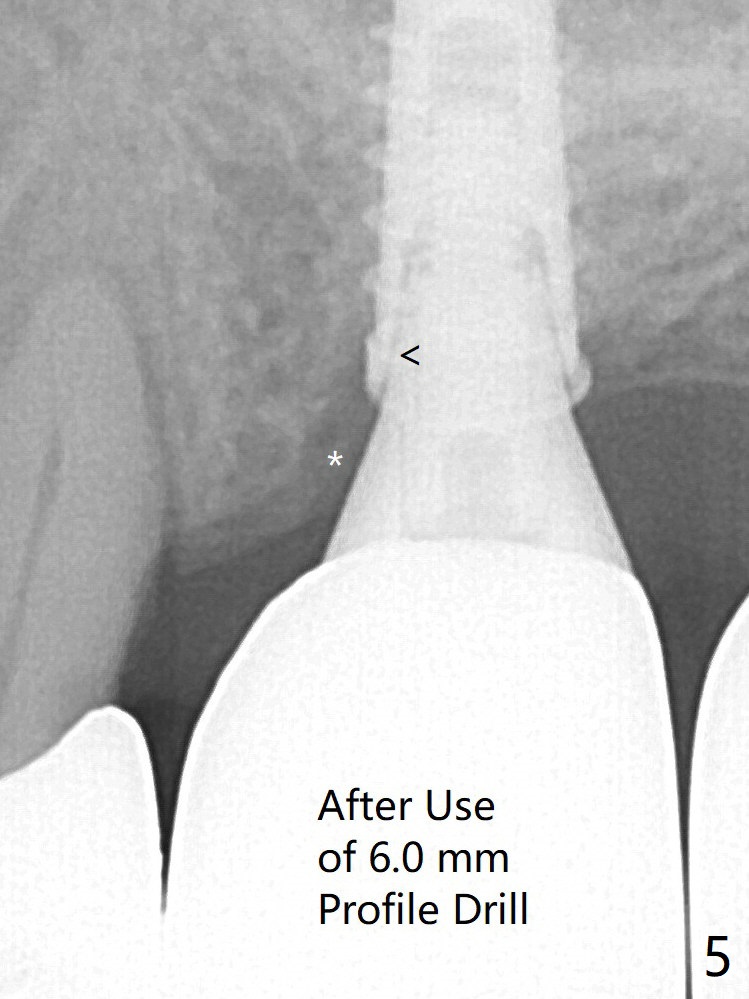

The crown/abutment at #14 is loose 1 year 10 months post cementation. After use of 5.5 mm profile drill, the crown/abutment is reseated, but the seating is incomplete (Fig.4 <) because of contact of the abutment with the mesial crest (*). A larger profile drill does not help (Fig.5). When a narrower abutment (4.5x7.5(3) mm) is torqued, it appears to be completely seated (Fig.6). After distal surface adjustment of the abutment, impression is re-taken. Depth Control Last Next Xin Wei, DDS, PhD, MS 1st edition 01/14/2020, last revision 01/14/2020